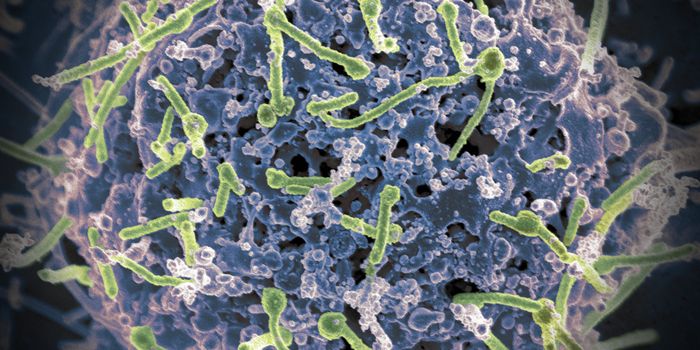

FEB 11, 2022MicrobiologyEbola virus has caused several major outbreaks in recent decades. Its high death rate and disturbing symptoms have made ...